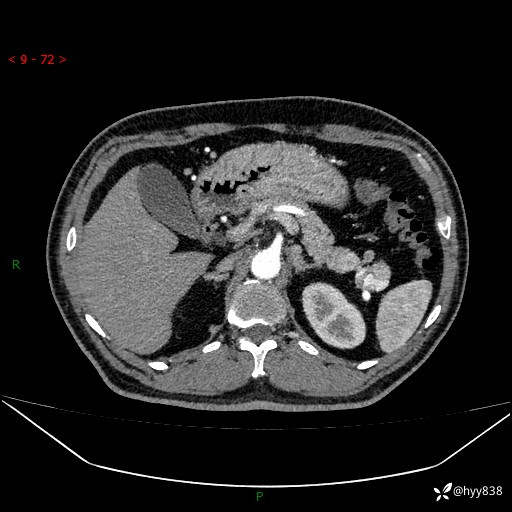

增强动脉期

静脉期